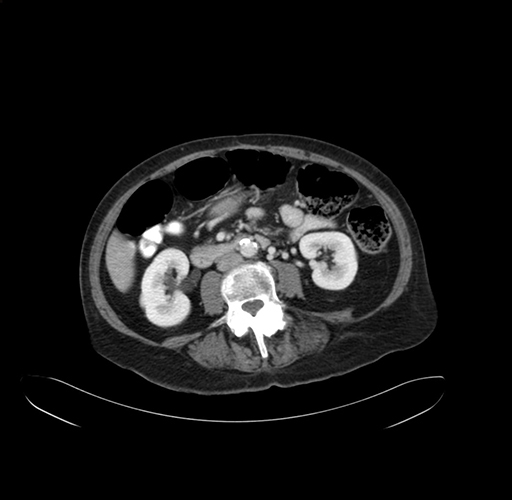

Axial Venous